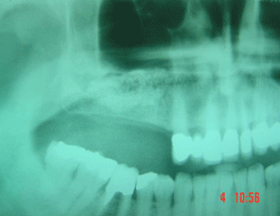

This X-ray shows (dotted area) where BIO-OSS bone grafting material has been surgically placed in order to lift the maxillary sinus floor and in that way increase the height of the jaw bone.

This X-ray shows the build up of bone after 6 months healing period, with sufficient bone height for safe placement of implants.